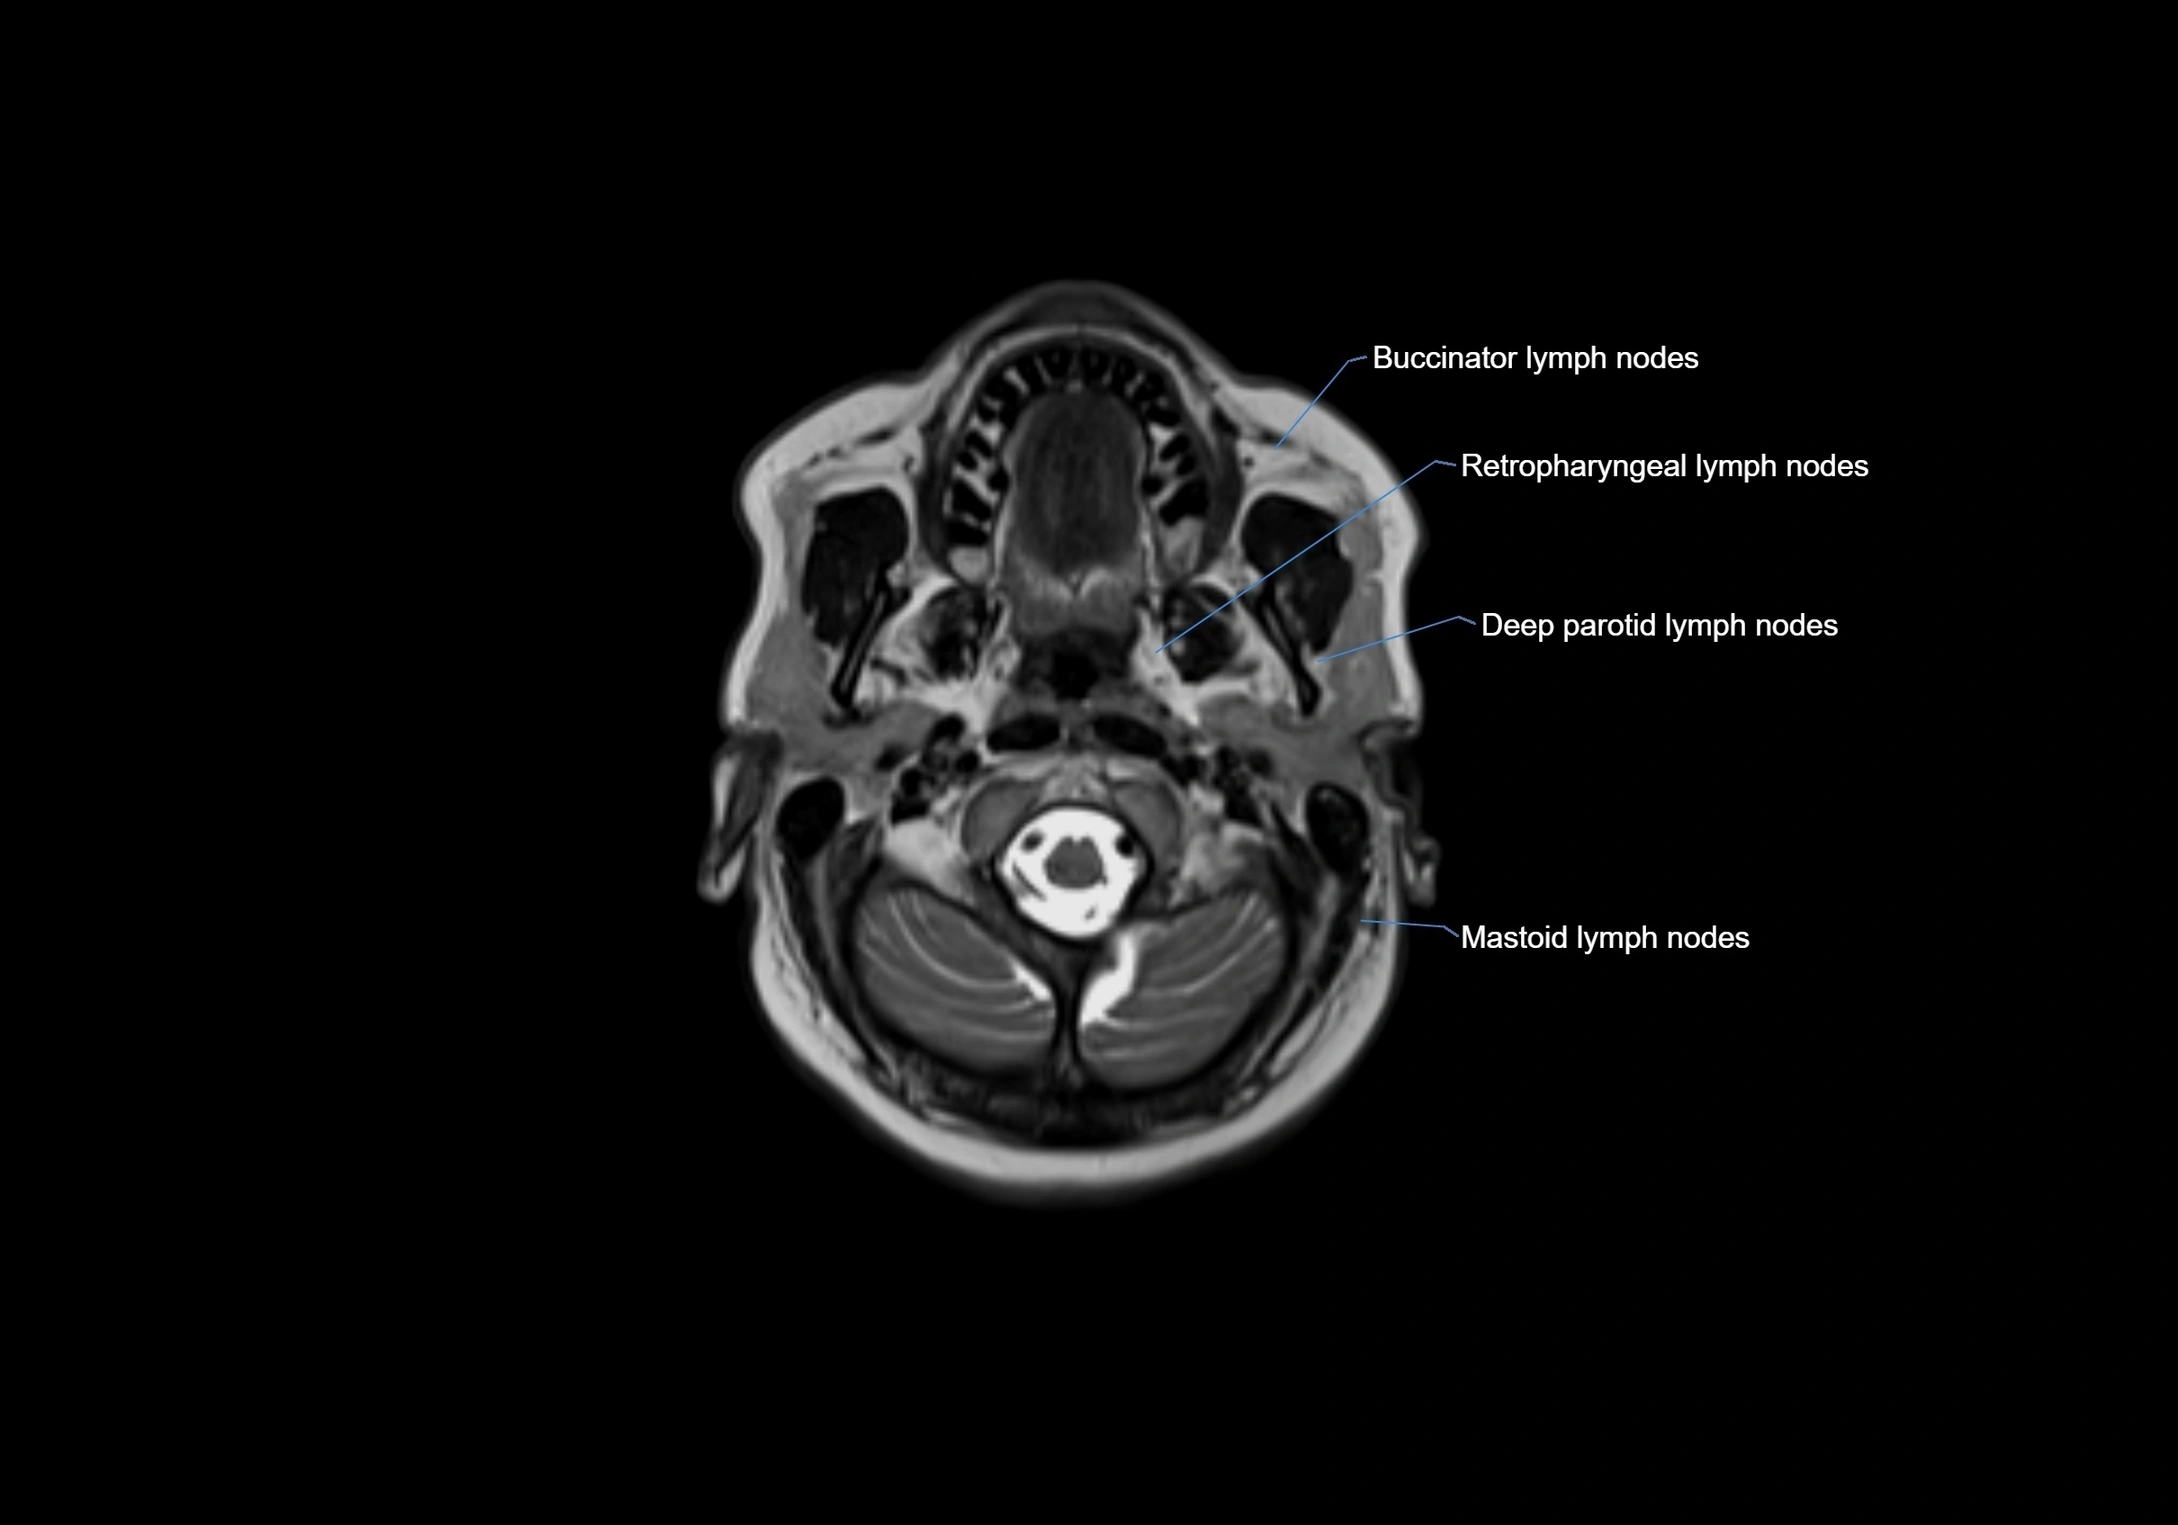

Location

• Found along primary lymph node chains, including preauricular, submandibular, parotid, and occipital regions

• Embedded in subcutaneous fat or superficial fascia, often lateral or posterior to primary nodes

• Variable in number; may occur unilaterally or bilaterally, depending on individual anatomy